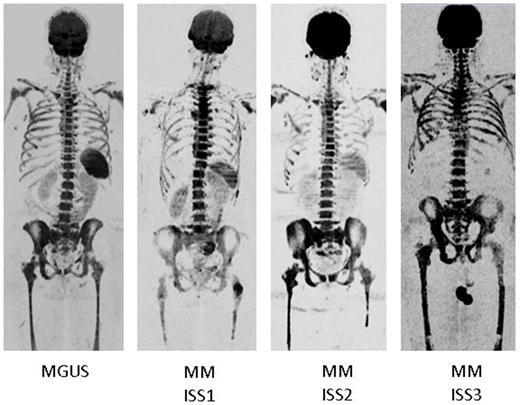

Results: Absence of the spleen signal on DWIBS was a frequent phenomenon in MM, seen in 71/295 (24%) patients. In all of these patients asplenia was excluded using alternative imaging techniques. Lack of a signal was highly positively associated with tumor-load parameters, such as the degree of BMPC infiltration (P=1x10-10) or International Staging System (ISS) 3 (P=0.0001). In contrast, it was not associated with age, gender, or the tumor progression markers gain(1q) and del(17p). Patients with absence of spleen signal experienced unfavorable outcome (hazard ratio of 1.8 for PFS and OS). In order to further investigate the biological underpinnings of this phenomenon we performed a differential gene expression analysis of purified CD138 MM cells. No differentially expressed genes were found between patients with and without spleen signal, suggesting that the absence of the spleen signal mainly reflected increased tumor burden rather than specific tumor features. As a proof of concept, we addressed the spleen signal in individuals with MGUS, and longitudinally in MM patients who presented with absence of the spleen signal at diagnoses. Indeed, in all 78 individuals with MGUS the signal was preserved, and the majority of MM patients showed re-appearance of the spleen on DWIBS during treatment as the tumor burden declined. Interestingly, re-appearance of the spleen was helpful to distinguish between malignant and non-malignant hyperintensities in the BM, making the spleen signal a promising parameter for MM follow-up investigations.